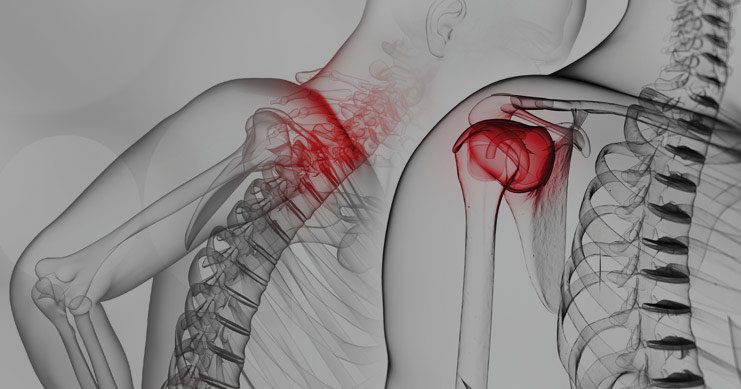

| Événement | Journées de l'AQMSE et de la FMOQ – Colonne cervicale et épaule – Montréal – COMPLET |

| Quand | 27 avril 2023 - 28 avril 2023 |

| Lieu | Holiday Inn & Suites Montréal Centre-Ville Ouest, Montréal |